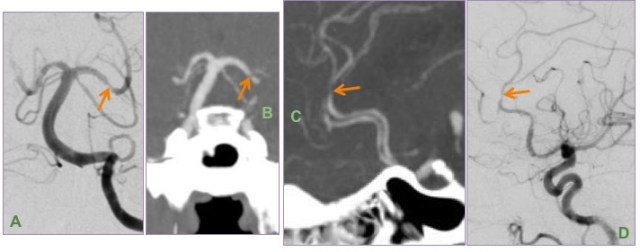

DSA (A & D) and MIP images from CTA brain (B & C) show multifocal short segment stenosis of medium-sized intracranial arteries of the anterior and posterior circulation.

Leptomeningeal biopsy showed vasculocentric transmural inflammation of the small arterioles with fibrinoid necrosis, consistent with vasculitis.

Vessel wall imaging may be performed in this case to look for homogeneous circumferential wall enhancement.